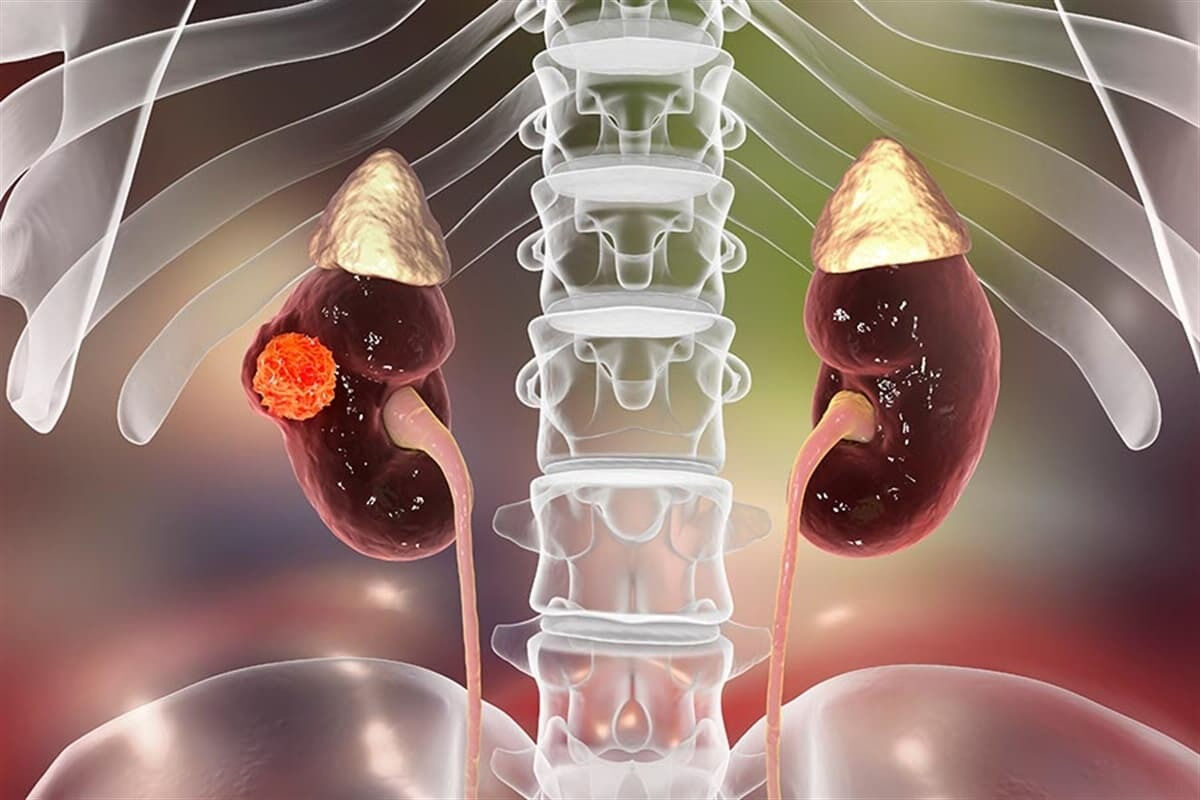

Süper aşı bütün tümörleri ortadan kaldırdı! 9 kanser hastası sağlığına kavuştu

Bilim adamlarının geliştirdiği kişiye özel kanser aşısı, 9 böbrek kanseri hastasında tümörü tamamen yok etmeyi başardı. Kanser hücrelerini hedef alan aşının Faz 2 çalışmaları sürüyor.

ABD’deki Yale Üniversitesinden bilim adamları tarafından kanser hastalığının tedavisinde çığır açacak bir çalışmaya imza atıldı. Araştırmacılar geliştirdikleri deneysel kanser aşısını Mart 2019 ile Eylül 2021 arasında çalışmaya katılan 9 böbrek kanseri hastasına enjekte etti. Bu kişilerin tümünün, Temmuz 2023’te yapılan üç yıllık takip muayenesinde kansersiz olduğu tespit edildi. Aşı, cerrahi müdahale sonrası kalan kanser hücrelerini hedef alarak sağlıklı hücrelere zarar vermeden ortadan kaldırdı.

Yale Kanser Merkezi ve Dana-Farber Kanser Enstitüsünce geliştirilen kişiye özel aşı, böbrek kanserinin nüksetmesini önlemede umut veriyor. Faz 1 çalışmasında, 9 hastadan hiçbirinde hastalık tekrarlamadı. Hastalar toplamda 7 doz aşı aldı. Dört hasta yalnızca aşı olurken, beş hastaya düşük doz bağışıklık tedavisi ilacı da verildi.

Aşı, tümöre özgü mutasyonların yüzde 65’ine kadarını tanıyıp hedef alarak bağışıklık sistemini harekete geçiriyor. Araştırmalar, aşının hem tek başına hem de bağışıklık tedavisiyle etkili olduğunu ve ciddi yan etkilere yol açmadığını gösterdi. Hastalarda yalnızca grip benzeri hafif semptomlar gözlemlendi. Çalışma Nature’da yayımlandı, ancak Faz 2 araştırmaları sürdürülen aşının etkinliğinin kesin olarak belirlenmesi için daha fazla araştırma gerekiyor.